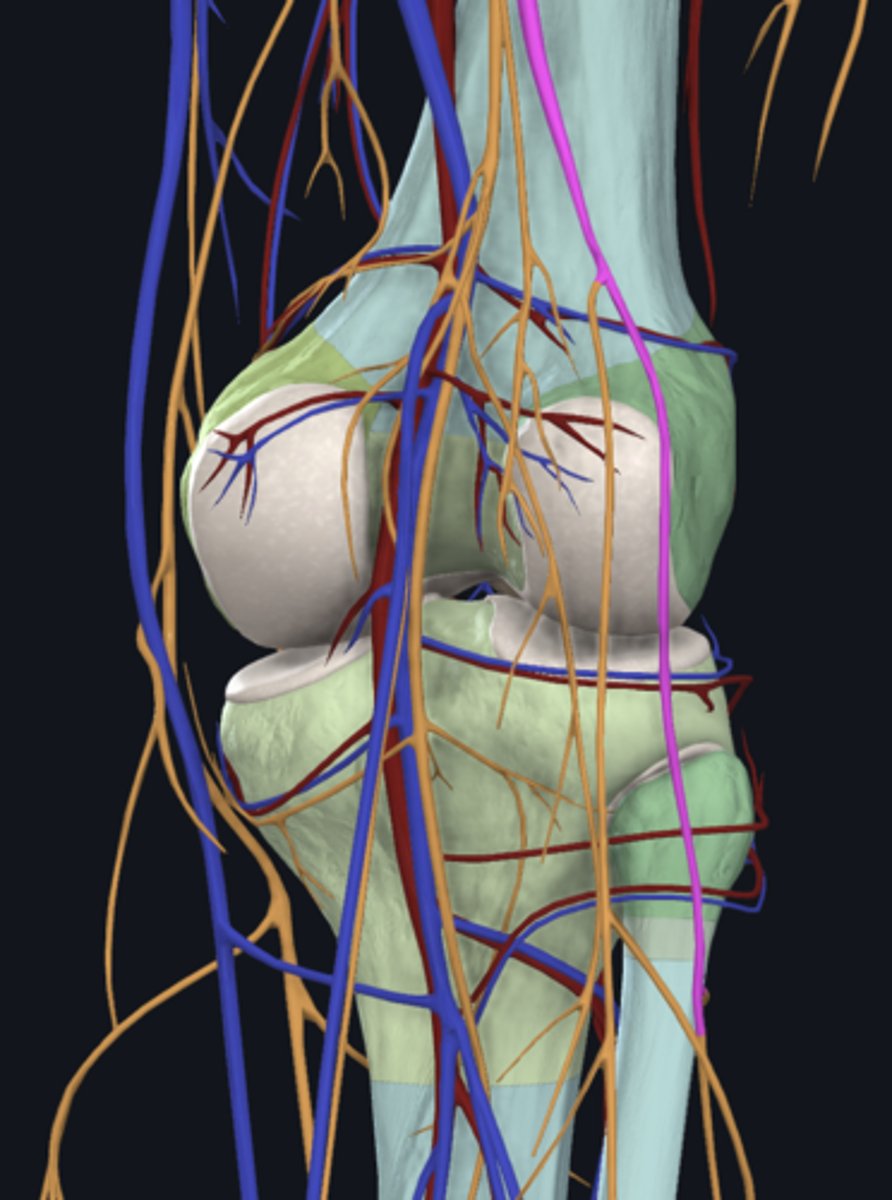

Popliteal artery

artery

Popliteal vein

vein

Tibial nerve

nerve